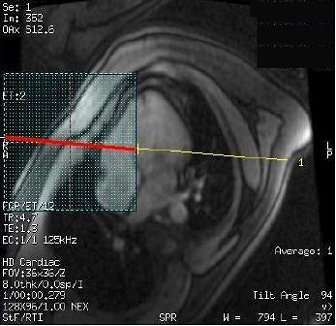

3. Place a small FOV shim volume over the heart.

• The shim volume FOV should be approximately half the size of the scan FOV. For example, if the scan FOV is 36 cm, then the shim volume FOV should be 18 cm. For more details, see Shim volume procedure.

Figure 1. Shim volume over heart